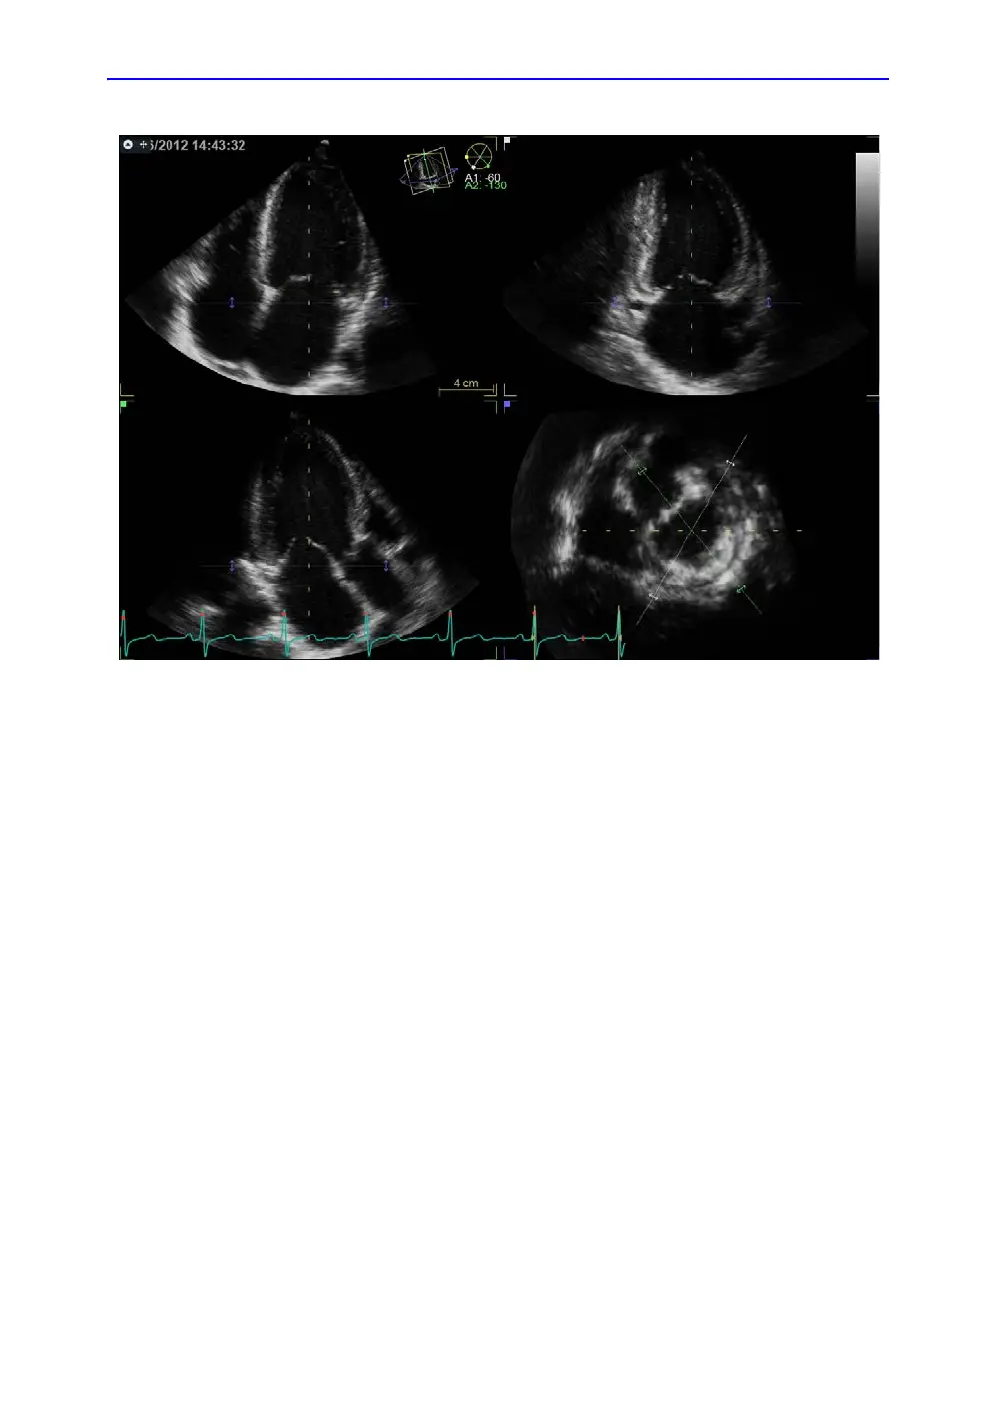

Figure 8-27. Slice alignment screen

Slice alignment

Slice alignment is used to identify the long axis of the left

ventricle, the three standard apical views and the

atrio-ventricular plane. Slice alignment performed and approved

before running 4D Auto LVQ is used by default, otherwise the

slice alignment is performed automatically. If necessary the auto

alignment can be further adjusted as follows:

1. Tilt and/or translate the apical views using the controls on

the panel or the trackball until the left ventricle is centered to

the center axis.

2. Rotate the apical views using the controls on the panel or

the trackball until the standard views are displayed.